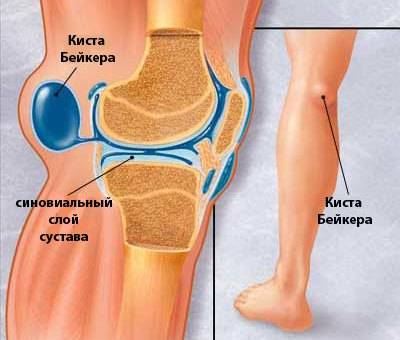

МРТ коленного сустава. Киста подколенной ямки (Беккера).

Заболевание коленного сустава под названием киста Беккера (по фамилии врача, открывшего эту болезнь) представляет собой доброкачественное новообразование, расположенное в подколенной ямке. Киста образуется в результате развития воспалительного процесса в межсухожильных сумках и представляет собой скопление синовиальной жидкости.

Киста Бейкера располагается в месте прикрепления сухожилий полупоперечной и икроножной мышц. Между ними в подколенной ямке есть межсуставная сумка, где и накапливается жидкость из воспаленного околосуставного пространства.

Что такое киста Бейкера коленного сустава?

В подколенной ямке формируется полость с эластичными мягкими стенками и плотной структурой. Такой эффект даёт скопление синовиальной жидкости. При разгибании колена киста Бейкера поддаётся пальпации, её легко визуализировать, но размеры выпота в поперечной плоскости обычно не превышают 3 см. Когда колено находится в согнутом состоянии, объём синовиальной полости становится меньше или полностью исчезает.

Опухоль доброкачественного характера, заполненная суставной жидкостью, которая локализуется на задней поверхности колена, называется киста Бейкера, или грыжа подколенной ямки.